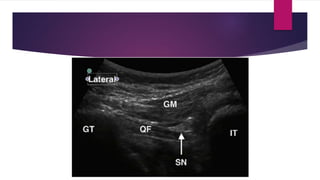

SCIATIC NERVE BLOCK (POSTERIOR APPROACH): USG

guided Subgluteal approaches